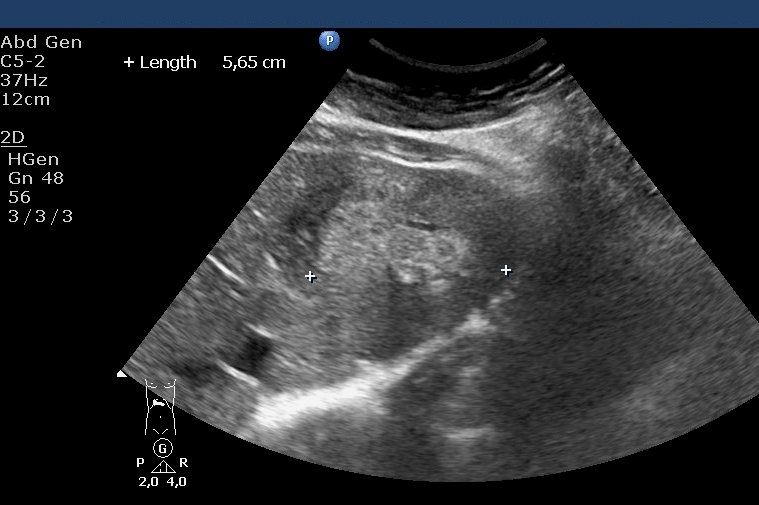

Typical apprearence includes a well defined, hyperechoic solide lesion measuring usually less than 2 cm in diameter (Figure 18).

Figure 18: Typical US image of a hemangioma in the sixth segment of the liver

In case of an atypical hemangioma (inhomogeous, mixed echostructure or hypoechoic appearence) additional imaging methods (multiphase MDCT, MRI) can be necessary, in addition in certain cases US guided biopsy can not be avoided in order to achieve the final diagnosis.

MRI is only needed in case of "atypical" hemangiomas, since ultrasound is the best imaging method for diagnosing the hemangioma. If the ultrasound finding is uncertain, dynamic CT (Figure 19, 20), afterwards nuclear imaging and biopsy are the appropriate choices.